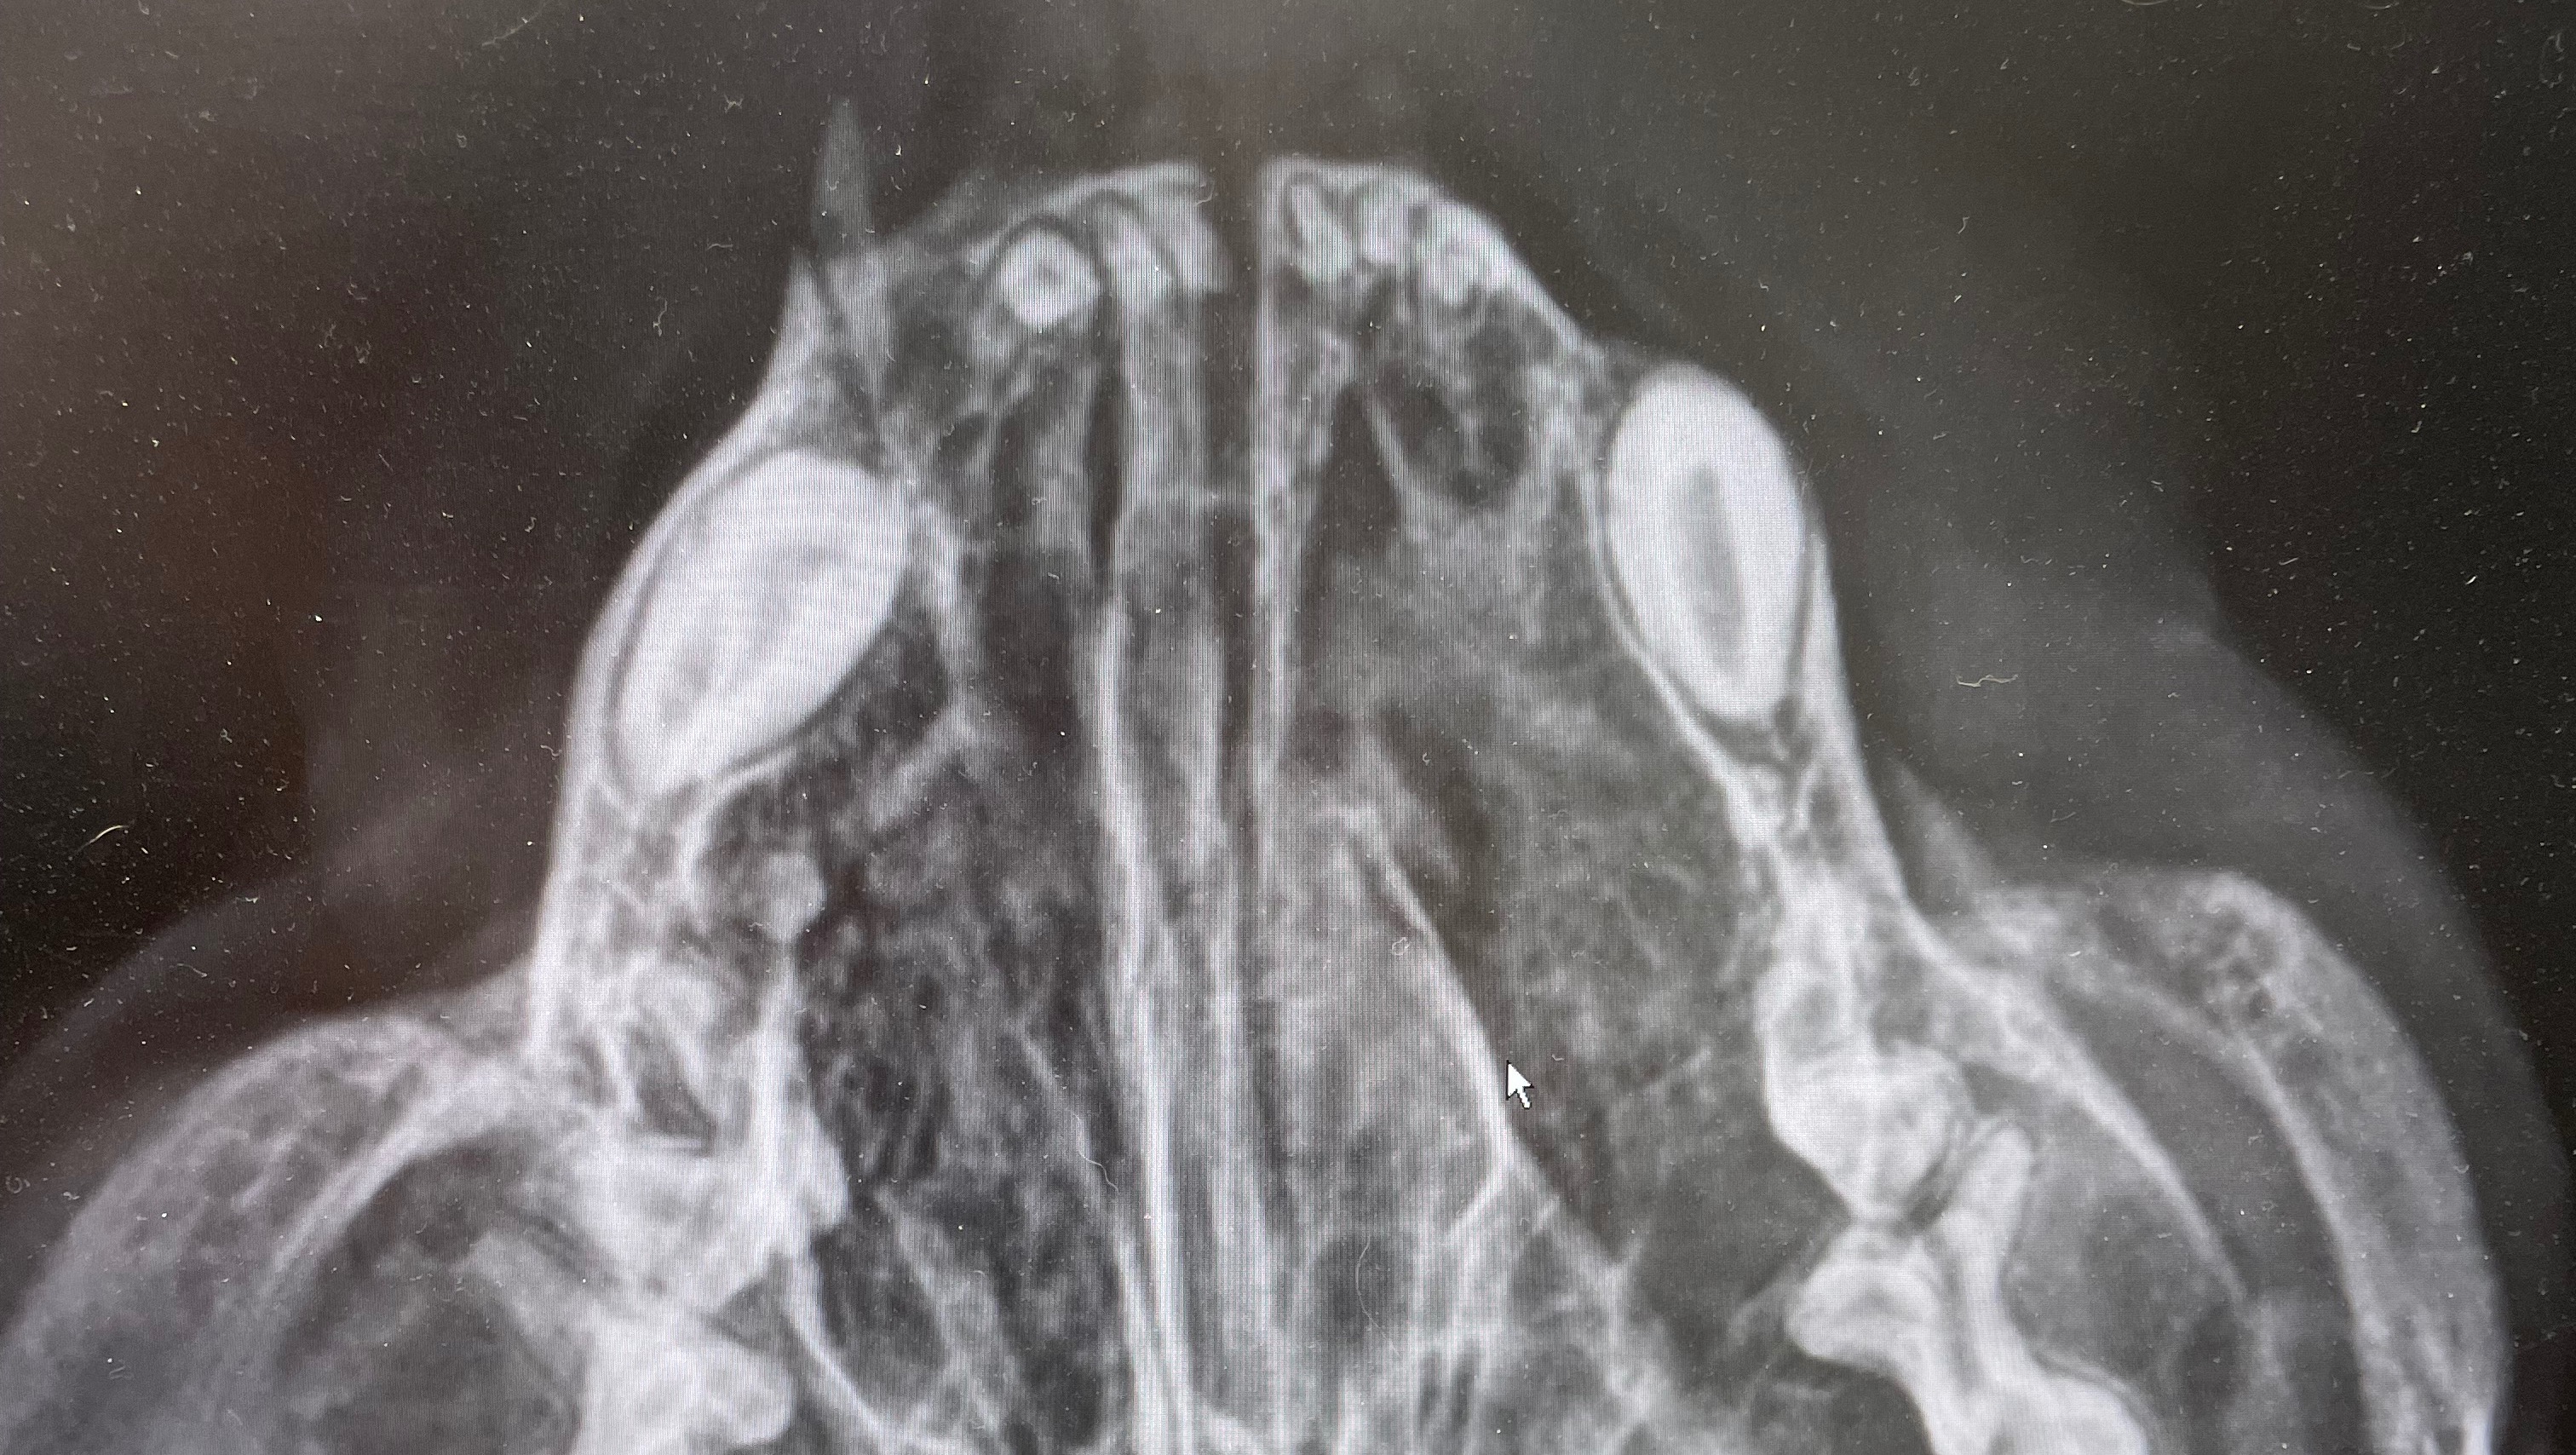

X-ray and invoices for transparent reference. more bills are incoming, only the first two are listed ($2000-ish total), and i'm about to pay the 3rd invoice for take home medications which is about $450. i'm also transferring him to a 24-hour spot, North Peninsula Emergency Vet Clinic, so he can have his breathing and surgery needs immediately addressed. Thank you for reading and following Rasi's Healing Journey.